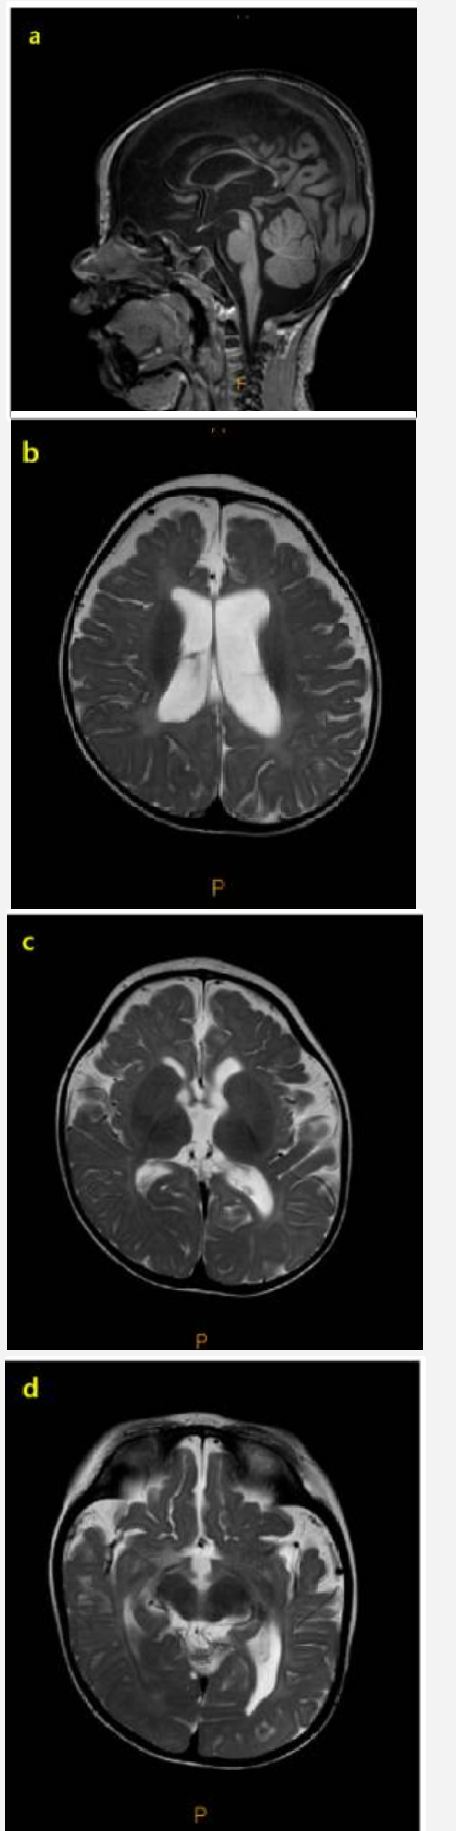

对患者进行了初步评估,以确定癫痫发作的病因和里程碑式的发育迟缓。脑MRI显示弥漫性脑萎缩,以脑脊液腔外扩大、脑沟明显、胼胝体变薄为特征(图1)。癫痫发作期间捕获了发作期脑电图(EEG),其特征是弥漫性棘波、多棘波和多波放电,随后是电衰减期。发作间期脑电图显示多灶性棘波放电,伴有高振幅背景活动,诊断为高度节律失常和婴儿癫痫痉挛综合征(图2)。患者接受氨己烯酸治疗,起始剂量为50 mg/kg/天,逐渐增加至150 mg/kg/天。然而,由于持续性癫痫痉挛,开始使用大剂量类固醇进一步治疗。经胸超声心动图和腹部超声检查未见异常。